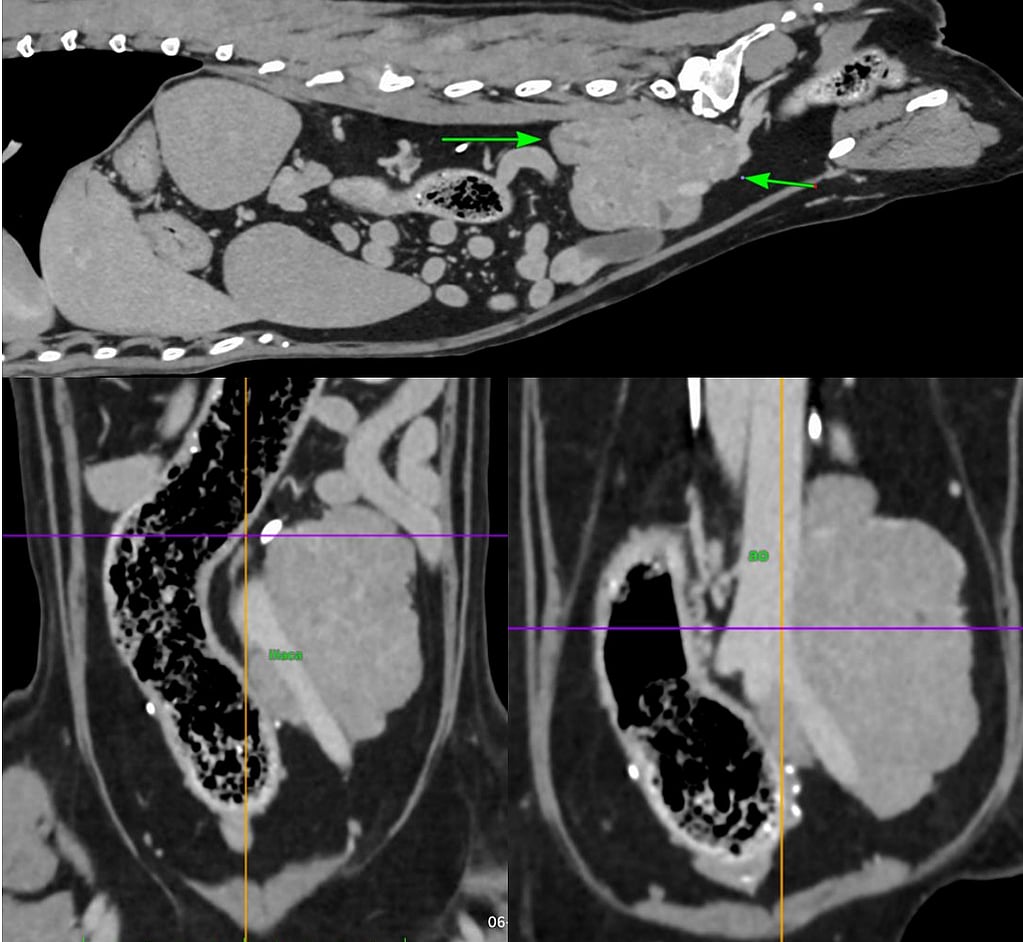

Elke 3 maanden kwam Kyra op oncologie controle. Begin januari 2025 kwam ze i.v.m. blaasproblemen. Bij het echografisch onderzoek door onze Europees Specialist Radiologie Susanne Boroffka werd er een enorm grote massa ontdekt achter in de buik. Dit bleek een sterk vergrootte lymfeklier te zijn. Uit de punctie bleek dat het ging om een uitzaaiing van de anaalzaktumor die 3 jaar eerder was verwijderd. Ook maakte deze tumor een hormoon dat zorgde voor te veel calcium in het bloed.

Kyra is vervolgens geopereerd door onze Europees Specialist Chirurgie Nicolien van Klaveren. De lymfeklier zat stevig vast aan zowel de aorta als de vena cava (twee grote belangrijke bloedvaten), maar met veel precisie en geduld kon deze volledig worden verwijderd. Kyra herstelde goed na de operatie en mocht dezelfde dag alweer naar huis. De lymfeklier is opgestuurd voor pathologisch onderzoek.